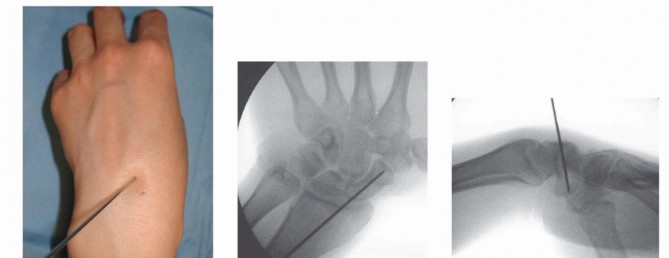

TECH FIG 4 • A-C. In the percutaneous volar approach, the guidewire is inserted into the scaphoid at the scaphotrapezial joint and into the center of the proximal pole. The wire should be inserted aiming for the Lister's tubercle. Alternatively, the guidewire may be placed directly through the trapezium into the scaphoid distal pole. 11 Advance the guidewire to the subchondral bone of the proximal pole.Place a second guidewire of equal length against the surface of the distal scaphoid, adjacent and parallelto the first guidewire. The difference between the lengths of the wires represents the length of the scaphoid.Subtract 4 mm from the length of the scaphoid to obtain the desired screw length. Use the cannulated reamer to ream the near cortex.Insert an Acutrak 2 or mini-Acutrak 2 screw (or a screw from the surgeon's chosen system) of appropriate length, remove the guidewire, and confirm satisfactory screw position and fracture reduction with fluoroscopy.P.337PEARLS AND PITFALLS